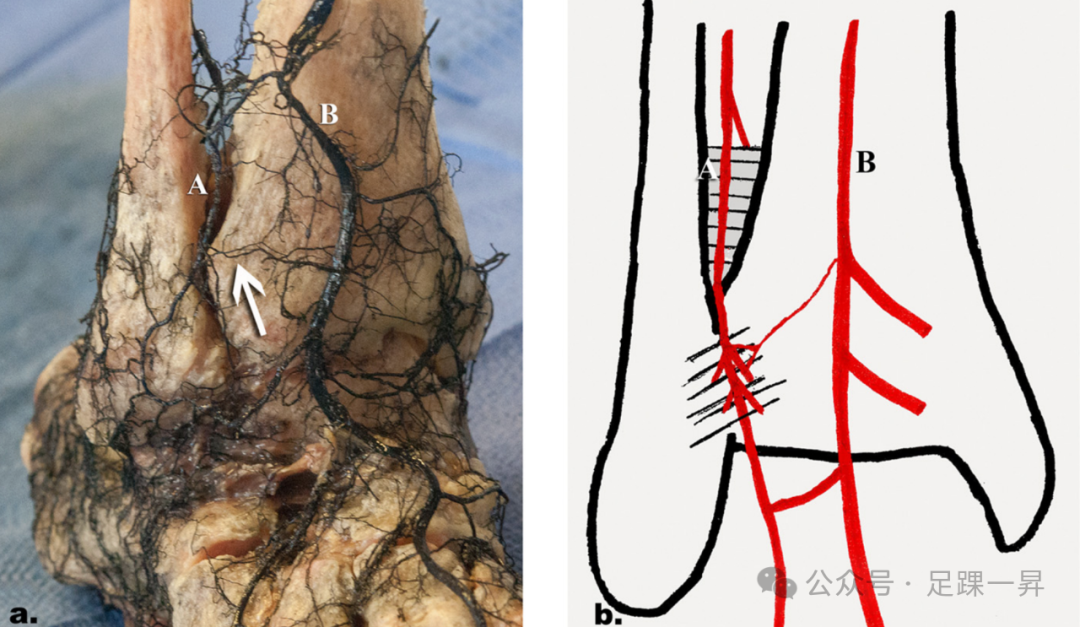

▲图示腓动脉(B)及其分支(A)穿过骨间膜至下胫腓前联合。

▲图示腓动脉(A)分为穿支(B)和后支(箭头)。穿支穿入骨间膜,距踝关节近端平均3cm。